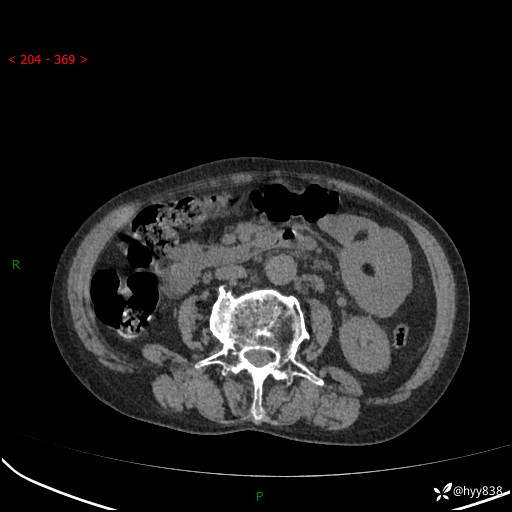

全腹部CT平扫